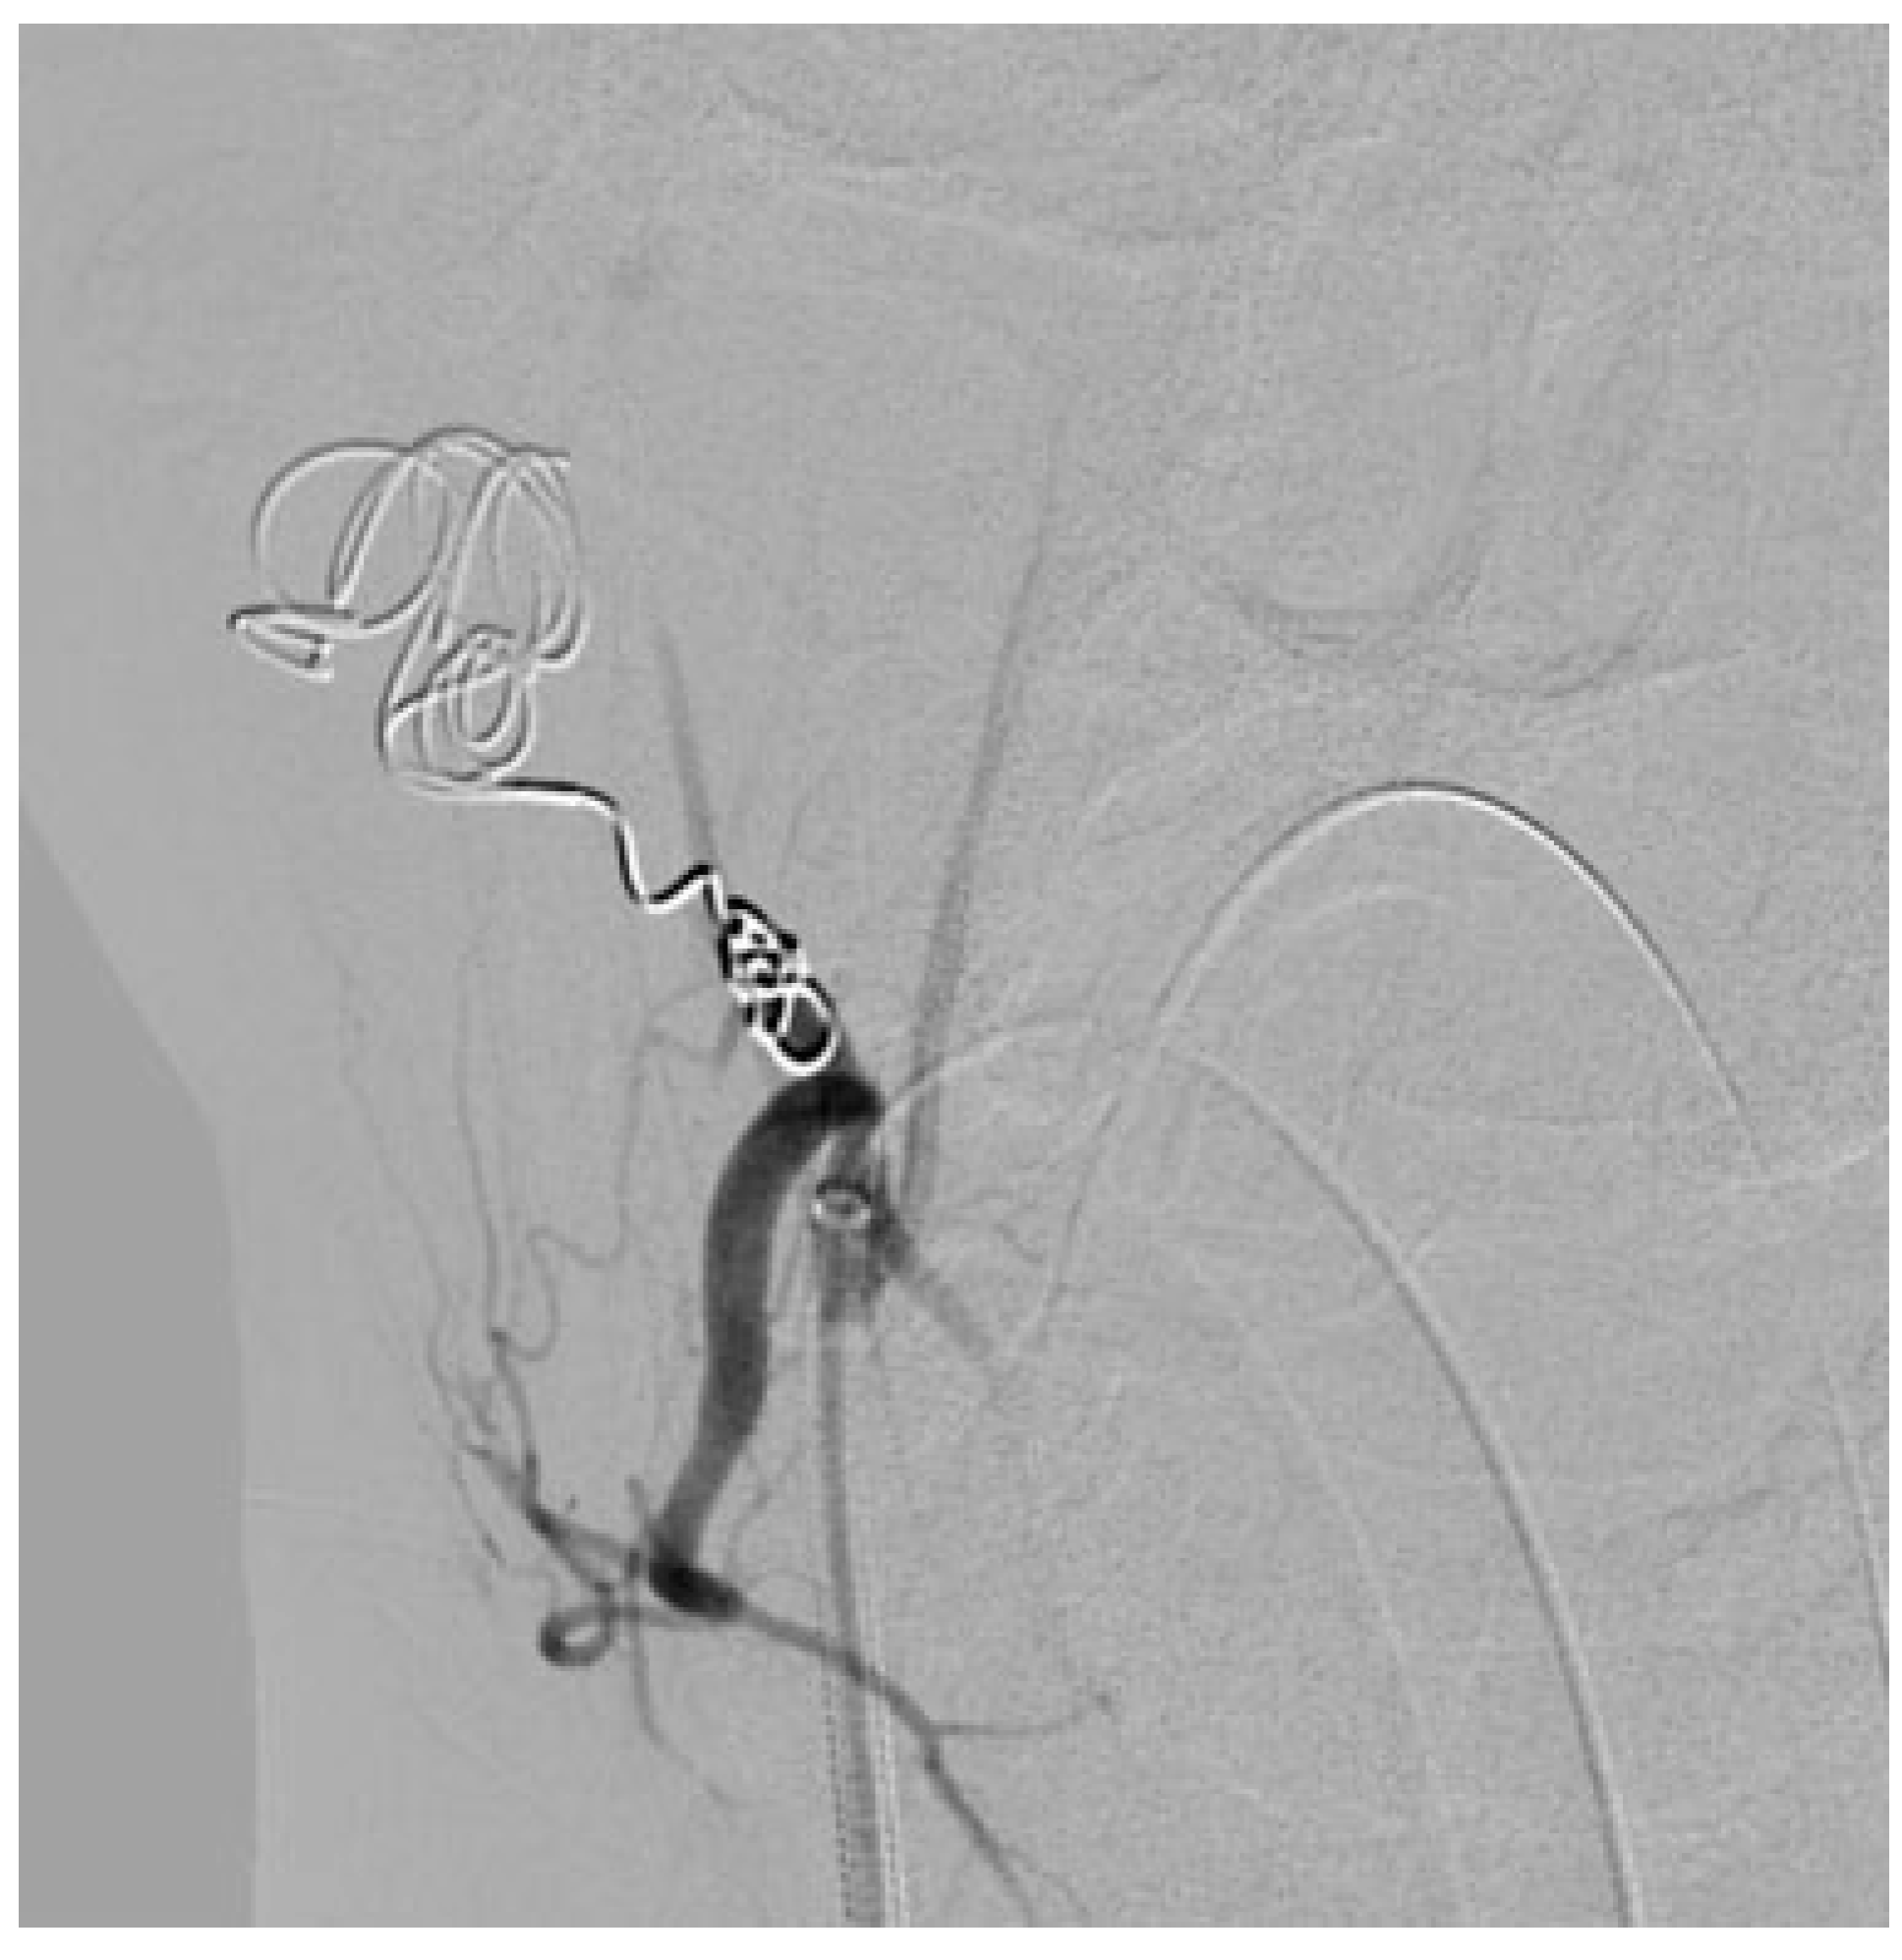

:Case Report